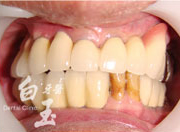

治療後